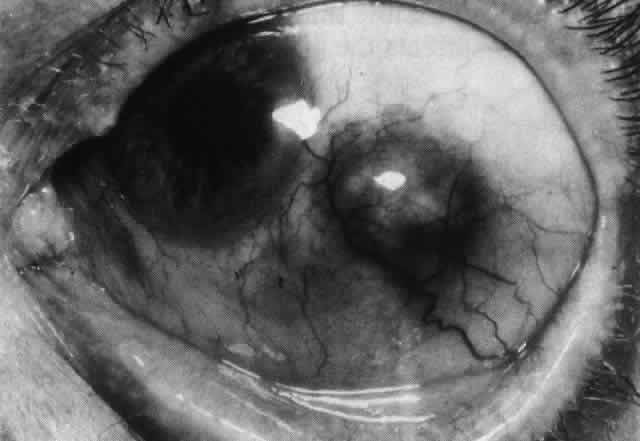

The sclera that is edematous is pushed forward, and the deep episcleral network is more congested than the superficial networks (Figs. 27 and 28). It is usually easy to ascertain by simple observation that the patient has scleritis and not episcleritis. However, it is not as easy to ascertain whether the patient has early necrotizing scleritis. It is in these patients that fluorescein angiography has considerable value, because the first changes are detectable in the ocular vasculature. Prompt and adequate treatment can prevent these changes from becoming irreversible.

Fig. 27. In scleritis, maximum congestion occurs in deep episcleral plexus, which is bowed forward by underlying scleral edema. Episcleral tissue is slightly infiltrated and superficial plexus is slightly congested (see Fig. 14). (Watson PG, Hayreh S, Awdry P: Episcleritis and scleritis. Br J Ophthalmol 52:278–279, 1968)

Fig. 28. Nodular scleritis. Both the anterior conjunctival slit and the deep scleral slit are displaced forward by the scleral edema. There is little separation between these two beams, indicating that all the edema is in the sclera and not in the overlying episclera. (Watson PG, Hayreh S, Awdry P: Episcleritis and scleritis. Br J Ophthalmol 52:278–279, 1968)

Nodular Anterior Scleritis

Although patients with nodular anterior scleritis resemble those with nodular episcleritis on cursory examination, detailed examination reveals marked differences. The nodule or nodules (they may be multiple) consist of scleral tissue that is immovable episclera is tightly adherent to the nodule, which is tender to the touch. Although the sclera sometimes becomes transparent below the nodule, it does not become necrotic, nor does the condition extend beyond the site of the nodule, as occurs in necrotizing scleral disease (Fig. 36).

(see Fig. 28; Figs. 34 and 35). The edematous

Fig. 34. Scleral edema has displaced all the vessel layers forward. Area surrounding the nodule is acutely inflamed.

Fig. 35. Multiple scleral nodules. Surrounding inflammation is deep and intense. (Watson PG: Management of scleritis. In: Recent Advances in Ophthalmology, Vol 5. London, Churchill-Livingstone, 1975)